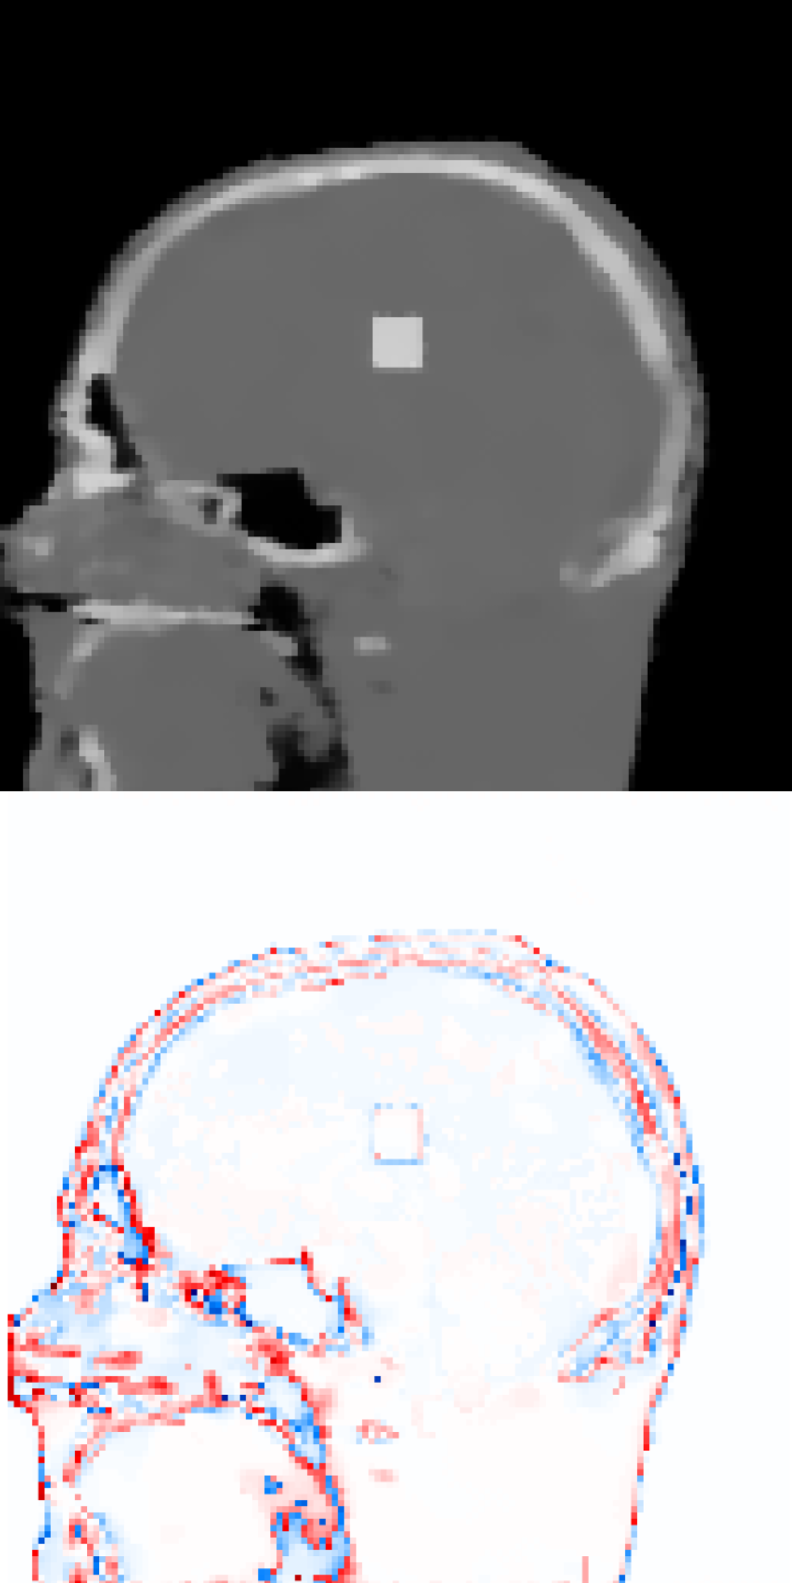

Figure 1 exhibits a slice of the reconstructed images using all the aforementioned algorithms. Here, (a) is the prior image 𝒙p\boldsymbol{x}_{p}, (f) is the ground truth, and the rests are the reconstructed images (top) with the corresponding reconstructions errors (bottom), all displayed using the same colorbar. Note that the error is just the difference between the reconstruction with respect to the ground truth image, so that high pixel intensity indicates inaccurate reconstructions and a fully black image would indicate a perfect reconstruction. This local error information is more informative than only displaying the error norms, or global error, since one can easily observe there is a high local difference between reconstructions.

Since this is a very undersampled dataset, FDK performs qualitatively poorly. Also for SIRT, and IRN-TV the quality drops significantly. The ASD-POCS-TV and ASD-POCS-PICCS are performing well, although a lot of texture information from the image is lost due to the smoothing process. However, the reconstruction time is higher than the other algorithms. The proposed algorithms perform better considering the available texture detail and the reconstruction time. Especially, the image in figure 1(h), IRN-PIPLE, is reconstructing the tumour better by preserving the texture information. Moreover, in figure 1(i), the tumour is more prominently visible due to the added TV regularization in the IRN-PICCS algorithm, however, with compromised original texture information of the image. Note that, for both proposed algorithms, the reconstruction time is in the range of 13 to 76 seconds only.

Figure 1: Reconstructed images using the digital head phantom data, with heavily undersampled projections (20 angles per set). The reconstructed images are shown in [0, 1]; difference images in [–0.5, 0.5].